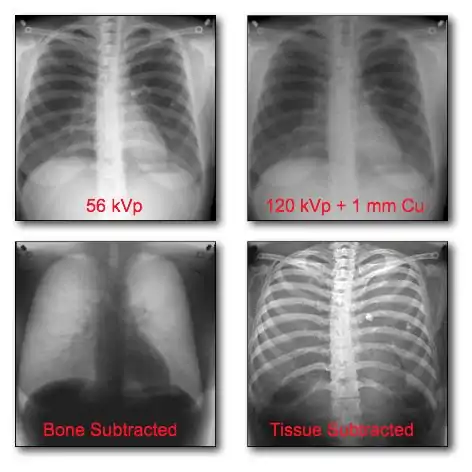

Dual-energy imaging can be used to eliminate bone information in an image, so that an image displaying tissues only is obtained. Alternatively, the technique can be used to generate the reverse effect where tissue information is eliminated and an image displaying bone only is generated. This latter option ideally allows the density of bones to be analysed. A theoretical background to this imaging technique will first be developed below with the discussion leading towards Dual-Energy X-Ray Absorptiometry (DEXA).

Dual-Energy Imaging